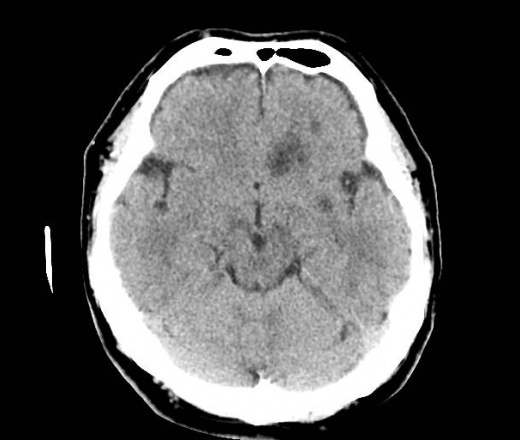

Пациент поступил 5.05.14 с жалобами на головную боль, головокружение, слабость в правой руке и ноге. Выполнена КТ головного мозга, данных за наличие ОНМК не обнаружил, только 2 постишемические кисты, в анамнезе инсульт в феврале 2014г. 18.05.14 повторно КТ в связи с нарастающей неврологической симптоматикой правостороннего гемипареза. В базальных ганглиях и лобно-теменной области слева выявлено наличие гиподенсных очагов, сливающихся в фокусы. Ишемический инсульт? Сначала иссл-ие за 18.05, затем за 5.05. Еще смущает увеличенный размер гипофиза. Буду рад любым комментариям. Просьба сильно не ругаться, это моя первая публикация.

Теперь иссл-ие на момент поступления 05.05.14

Довольно необычные по локализации очаги. Похоже на ишемический инфаркт на границе бассейнов СМА и ПМА. Такие инсульты бывают гемодинамическими, т.е. происходящие не в результате тромбоза артерии, а в результате резкого снижения кровотока, обусловленного, как правило, нарушениями работы сердца.